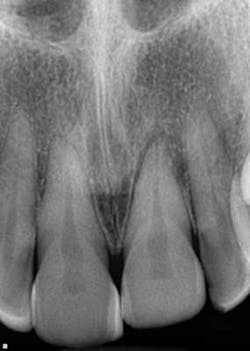

A healthy 7-year-old female presented directly from school with her father stating that she fell off the monkey bars. This was her first visit to the dentist. Initial exam revealed that tooth No. 8 was partially avulsed (Fig. 1) with only a slight attachment to the gingiva. All other teeth appeared clinically normal. Radiograph assessment revealed a large open apex on No. 8. The patient was given a local. The clot was removed and the area irrigated with a saline rinse. Next, the tooth was gently repositioned in the socket with slight compression of facial and lingual alveolar processes. A nonresilient wire splint was placed from NOs. 7 through 9. The patient was given an Rx of antibiotics for potential infection. A one-week assessment revealed a significant decrease of swelling with No. 8 appearing fairly stable. After eight weeks, tooth No. 8 had a slight delay to cold testing with all other teeth testing normal. The splint was removed. It was discussed with the father that the delayed response could be attributed to the healing of pulp or potential pathology. A two-month follow-up was recommended.